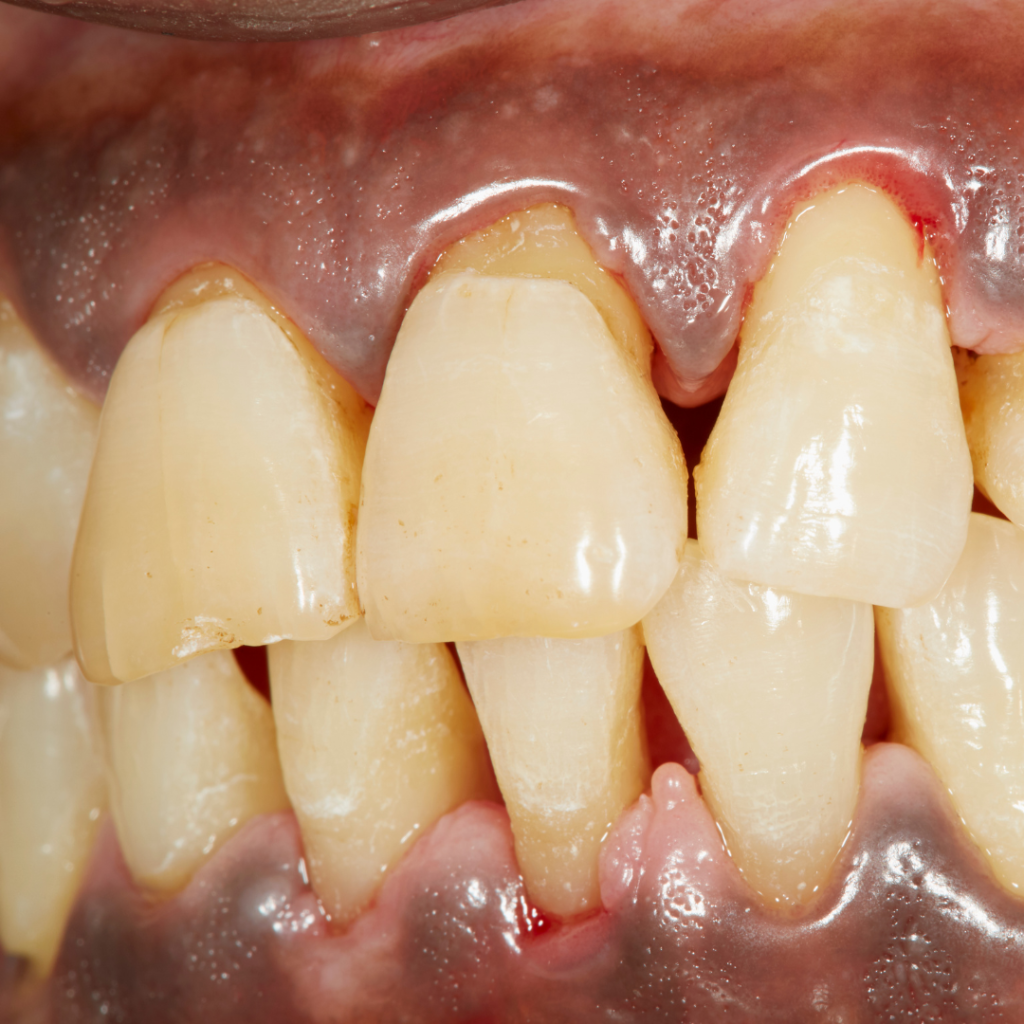

Periodontite – É uma doença inflamatória crónica que surge da evolução de uma gengivite não tratada. Esta doença leva à retração da gengiva e à perda do osso de suporte dos dente